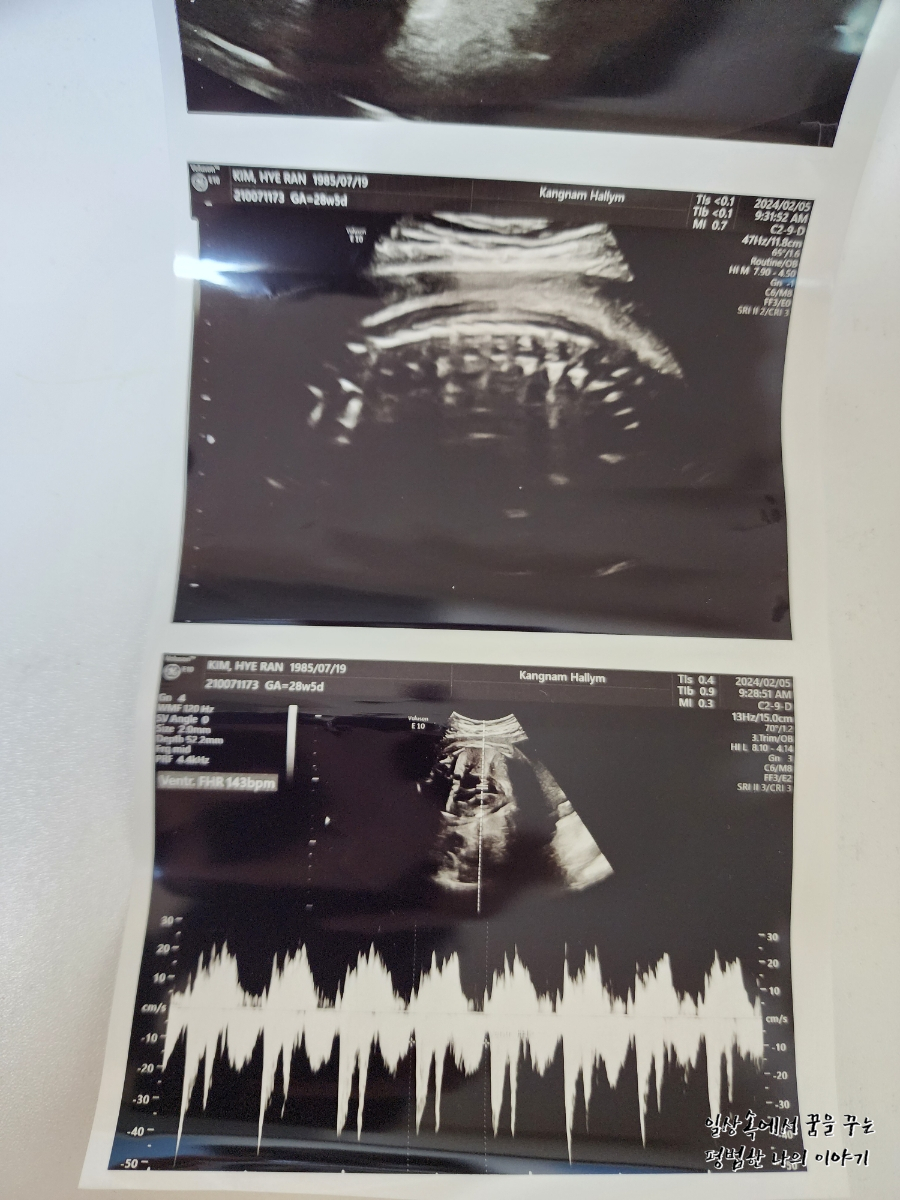

FHR(Fetal Heart Rate, 심장박동 수): 143bpm